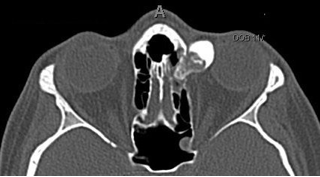

Figures 2, 3, and 4: Axial and coronal CT images demonstrating the ill-defined hyperosteotic lesion in the superior medial orbit with extension into the ethmoid sinus (click on Image for enlargement)

Figure 2, see caption above Figure 3, see caption

figure 4, see caption